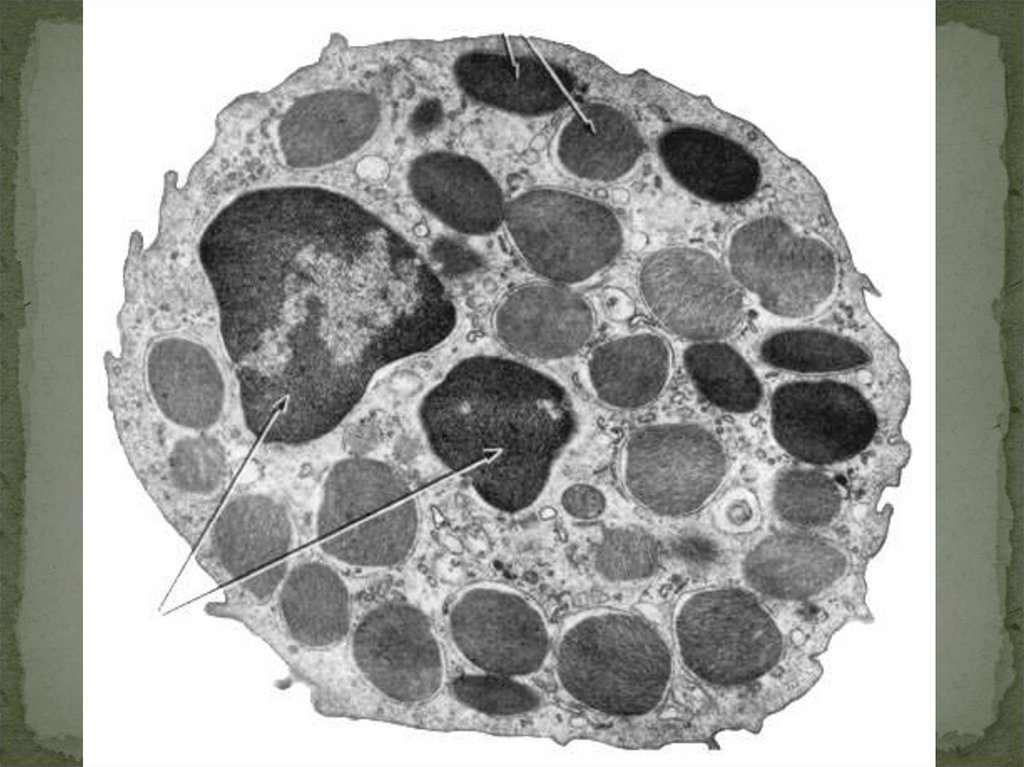

37. ОБРАЗОВАНИЕ ТРОМБОЦИТОВ

38.

39.

40.

41. МЕГАКАРИОЦИТ В ТКАНИ ЛЕГКОГО ПРИ ТРАВМЕ ККМ

42.